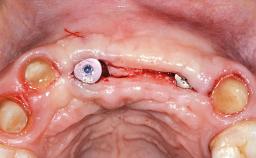

This 20-year-old woman was referred to our department in July 2006. Four months earlier, she had experienced dental trauma to the anterior maxilla when traveling in South America. The emergency treatment included emergency root canal treatment of teeth 12 and 11. Tooth 21 was also subjected to endodontic treatment later. At the initial examination, the patient was not in pain but reported increased mobility of tooth 12. The clinical examination revealed a high smile line, medium thickness of the soft tissue, and rectangular tooth forms. Discoloration of tooth 12 was evident. The periapical radiograph provided by the referring dentist indicated a fracture line at both teeth 12 and 11. A cone-beam computed tomography (CBCT) scan confirmed these fractures. No pathology was found to be associated with tooth 21.

Bone Augmentation Horizontal|Simultaneous

Augmentation Materials Autogenous chips|Xenogenous|Membrane

Soft Tissue Anatomy Intact Defective

Bone Volume Horizontally and vertically sufficient Horizontally deficient Deficient vertically or deficient vertically AND horizontally

Bone Volume Deficient horizontally, allowing simultaneous augumentation